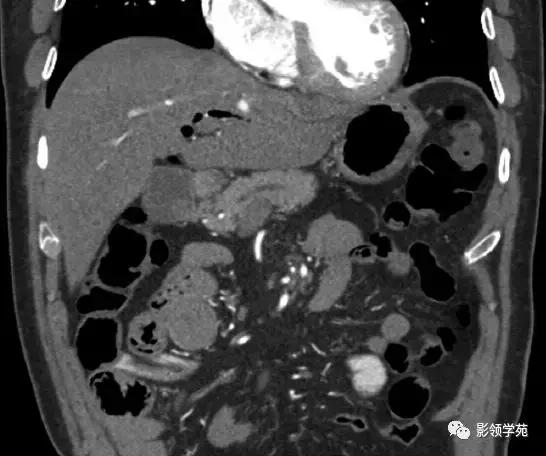

急性水肿型胰腺炎:CT平扫,胰腺明显肿胀,密度尚均匀,周围见条片渗出。

急性坏死型胰腺炎:CT平扫,胰腺密度不均匀减低,胰腺边界模糊,胰腺周围较多渗出积液,肝周可见积液。